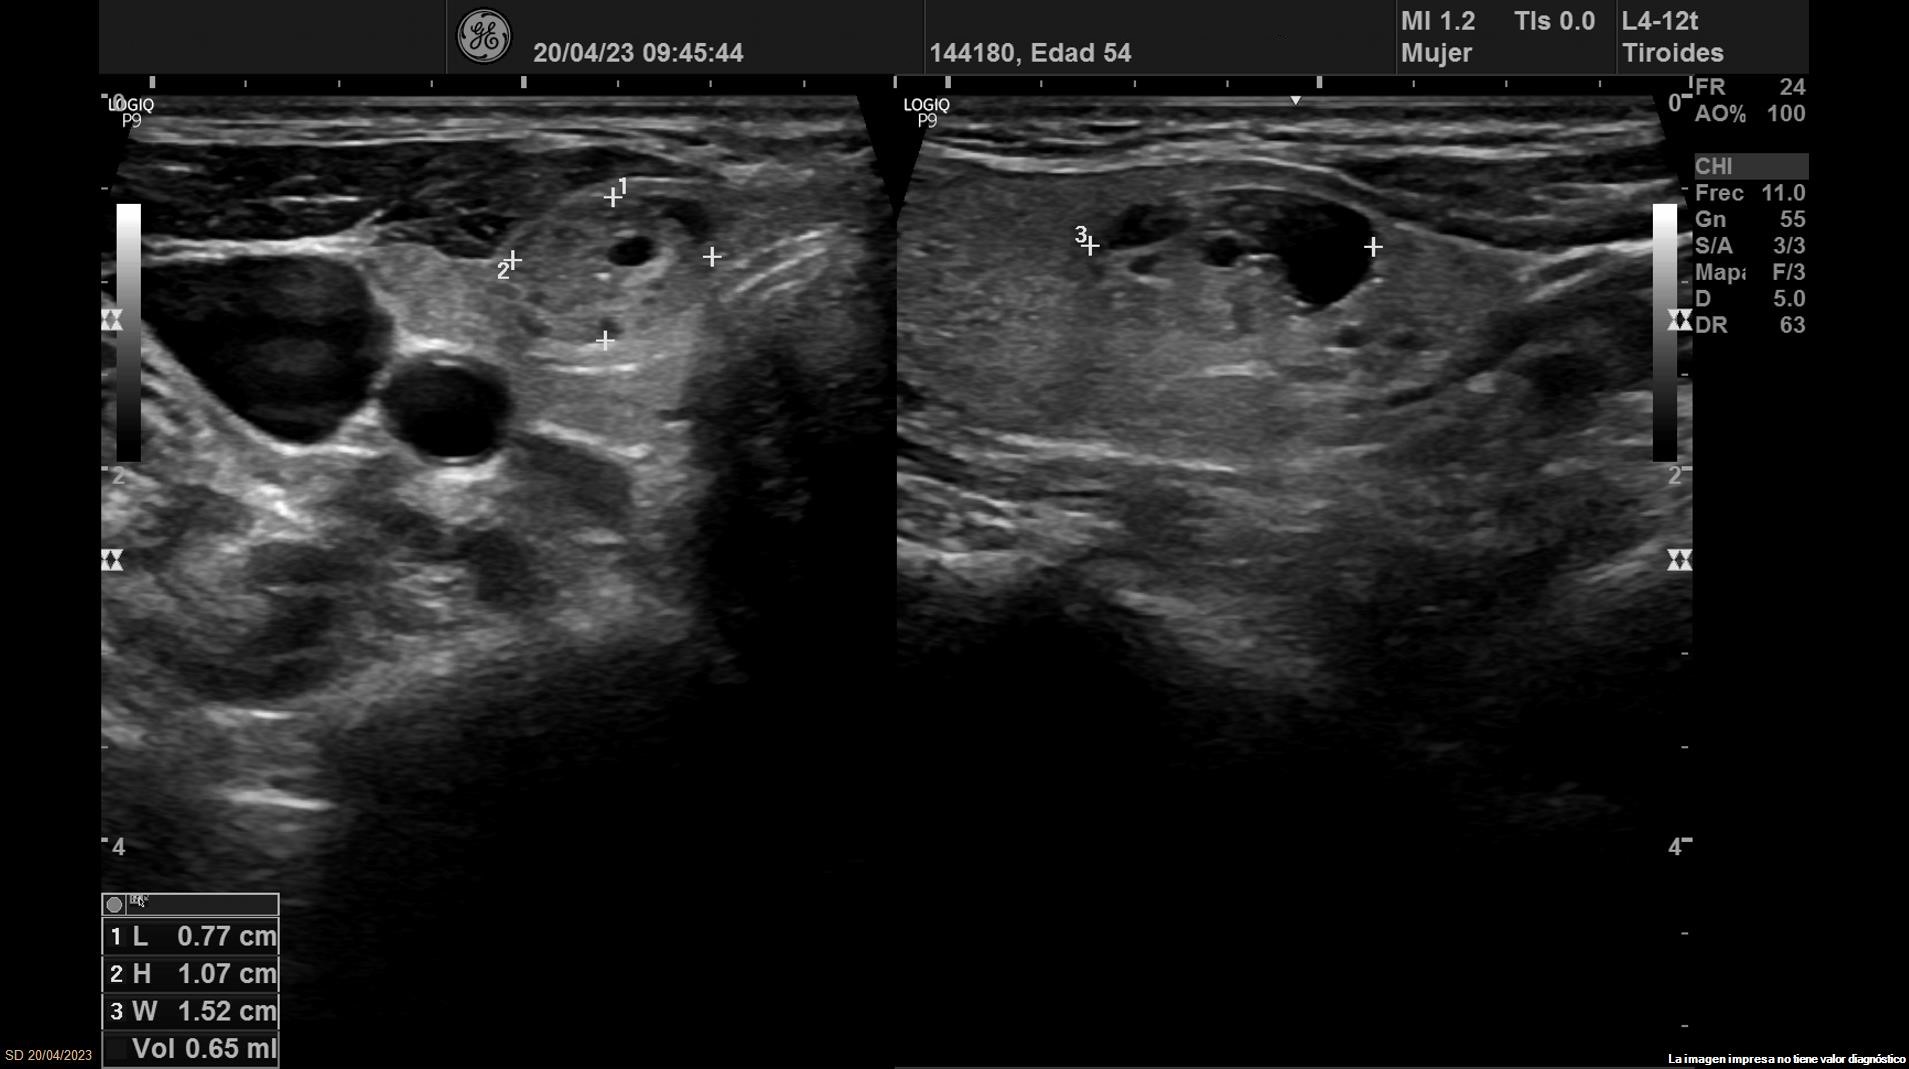

• Lóbulo tiroideo izquierdo: tamaño normal. En la mitad inferior se objetiva un nódulo de 11 x 14 x 20 mm (Vol 1,52 ml), bien definido, sólido e iso/hiperecoico, con halo fino hipoecoico, sin calcio y con vascularización de predominio periférico (ATA: baja sospecha).

• Lóbulo tiroideo derecho: tamaño normal. En tercio inferior nódulo único espongiforme con área quística inferior que mide 15 mm de diámetro mayor longitudinal (ATA: baja sospecha).